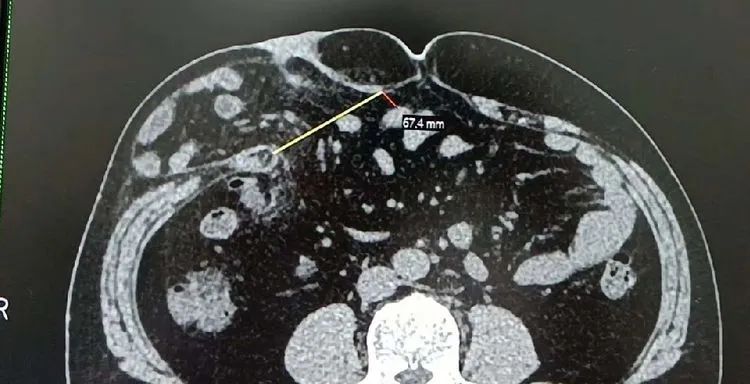

因“反複腹痛1年餘,再發1周”,黃師傅(化名)前往醫院就診,查體:腹平,未見腸型及蠕雲波,右季肋區飽滿,可觸及一5*7cm左右質軟包塊,觸痛陰性,腹軟,肝脾肋下未及,劍突下及臍周深壓不适,餘腹無明顯壓痛、反跳痛及肌衛,Murphy症(一)。CT可見:右腰部軟組織變薄,部分脂肪組織疝入皮下,疝口寬約74mm。影像學診斷:右腰部脂肪疝。